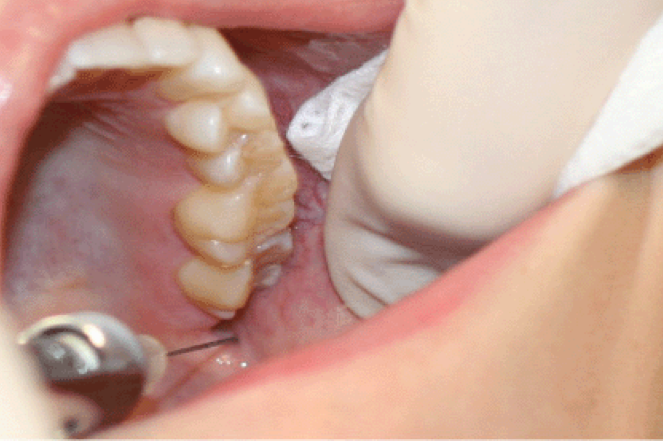

Target Site: Mental nerve as it exits mental foramen (between apices of the 1st and 2nd premolar)

mental foramen

mental/incisive nerve block